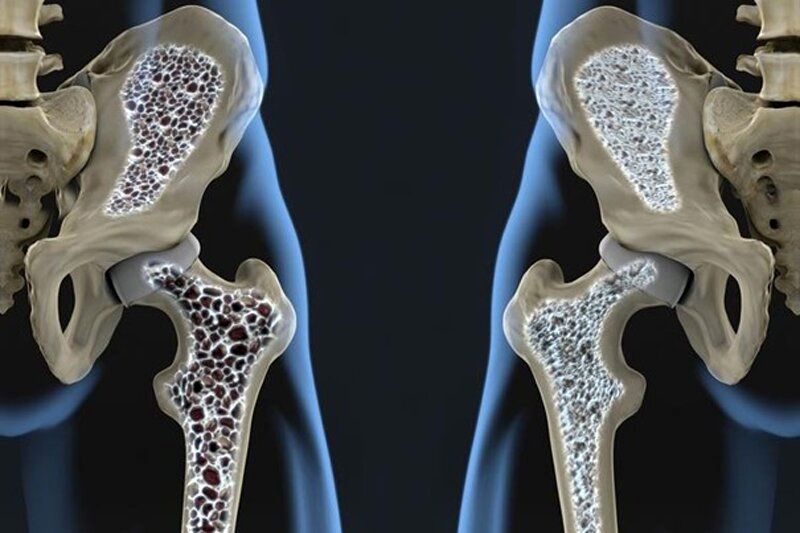

وی با بیان اینکه پوکی استخوان به معنای از دست دادن استحکام طبیعی استخوان و افزایش شکنندگی آن است، افزود: نازک شدن ستونهای استخوانی موسوم به ترابکولار موجب کاهش استحکام استخوان شده و به بروز استئوپروز میانجامد؛ بهطوریکه از هر سه زن یک نفر و از هر پنج مرد یک نفر ممکن است به این بیماری مبتلا شود.

این عضو هیئت علمی دانشگاه علوم پزشکی جندی شاپور اهواز تصریح کرد: پوکی استخوان تا زمانی که منجر به عوارضی مانند شکستگی نشود، ممکن است سالها بدون علامت باقی بماند. شایعترین محلهای شکستگی شامل ستون فقرات، لگن و مچ دست است و شکستگیهای مخفی ستون فقرات میتواند با کمردرد، کوتاهی قد یا قوز کمر بروز کند.